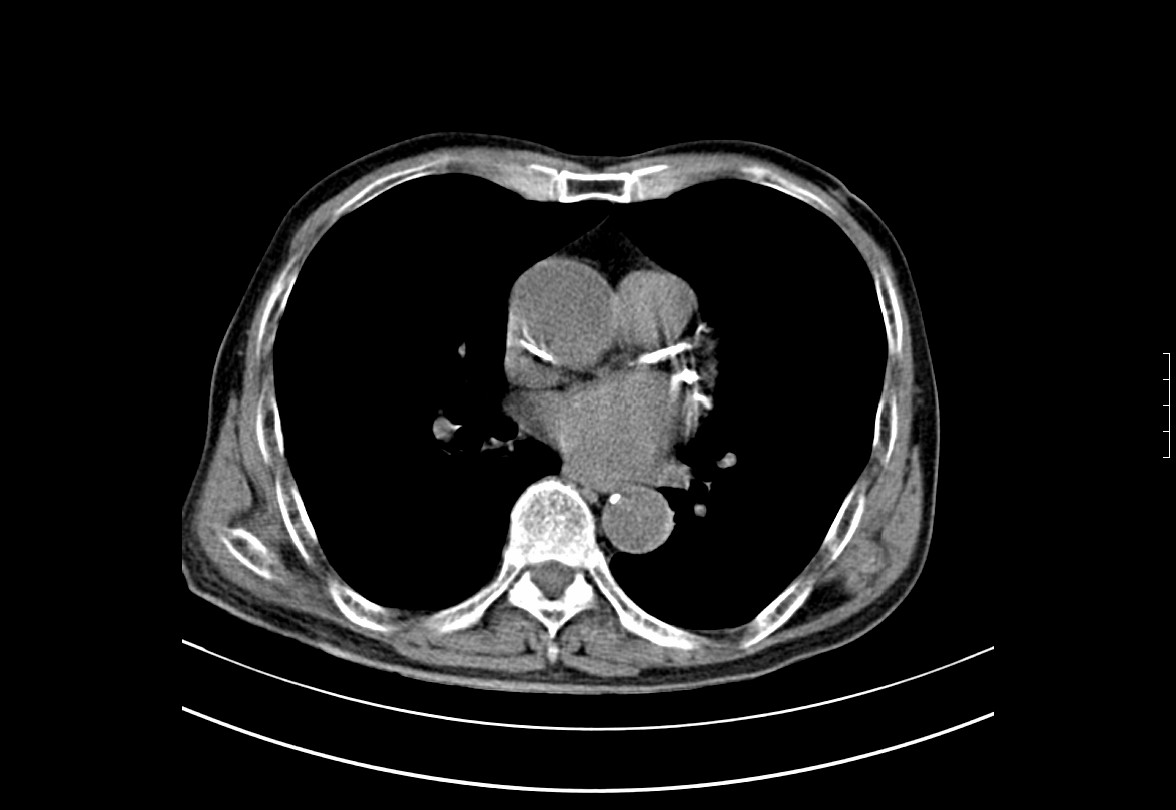

CT50900:男.85Y,体查发现左肺占位。

左肺下叶背段可见结节,边缘不规则,内见空泡征,两上肺见少许纤维索条影,主冠脉钙化,考虑左肺占位---肺癌?

左侧肺泡癌不排除。

2.左肺肺癌可能性大。

1、右上肺陈旧性结核。

1.气管内痰块?气管肿瘤?建议支气管镜。